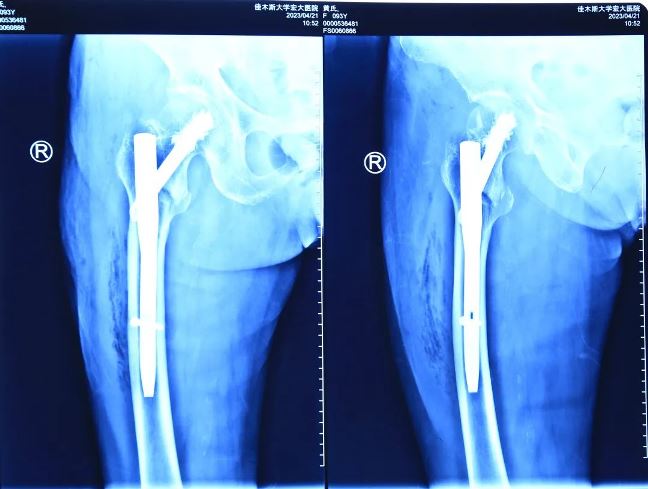

秉著視患者如親人的態(tài)度,向患者家屬詳細(xì)解釋了病情以及并發(fā)癥可能性,并告知了高齡體弱患者手術(shù)存在的風(fēng)險(xiǎn)。根據(jù)患者病情,喬院長建議為患者行右股骨粗隆間骨折閉合復(fù)位髓內(nèi)針內(nèi)固定術(shù)(APFN)。手術(shù)全程僅用不到1小時(shí),手術(shù)過程安全、無痛,固定效果良好?;颊咝g(shù)后第二天即可下地活動(dòng),患者的女兒激動(dòng)地說:“醫(yī)生,謝謝你們!真是太幸運(yùn)了,我母親可以在攙扶下站立走路了,感謝你們,是你們的精湛技術(shù),讓我的家庭再次圓滿”。

術(shù)后影像

隨著醫(yī)療技術(shù)手段及綜合醫(yī)療水平的不斷提高,年齡不再是手術(shù)禁忌證。佳木斯大學(xué)宏大醫(yī)院骨科團(tuán)隊(duì)已成功救治多例85歲以上超高齡粗隆間骨折患者,充分彰顯出醫(yī)院骨科團(tuán)隊(duì)的技術(shù)實(shí)力。目前,對股骨近端骨折采取APFN髓內(nèi)釘+骨水泥加強(qiáng)固定手術(shù)這一先進(jìn)治療方法,具有手術(shù)操作簡單、手術(shù)時(shí)間短、固定牢靠、對骨強(qiáng)度破壞小、出血少、骨折愈合率高等優(yōu)點(diǎn),適合于高齡股骨粗隆間骨折患者的手術(shù)要求,是一種值得推廣的骨科手術(shù)技術(shù)。